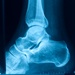

Have you ever had an Achilles problem? Is PRP therapy hype or hope?

Are platelet-rich plasma injections viable for Achilles tendon injuries?